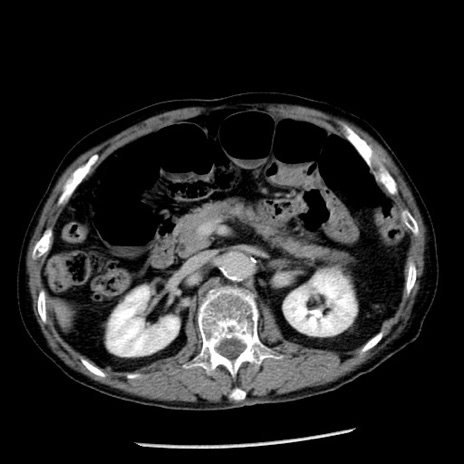

症例26(横断像)

【症例】80歳代男性

【主訴】嘔吐

【現病歴】昨晩2回嘔吐あり、今朝になっても嘔吐あり。来院。

【既往歴】胃潰瘍

【身体所見】意識清明、BT 37.6℃、BP 166/95mmHg、HR 100bpm、SpO2 97%、腹部:平坦・軟、腸蠕動音聴取良好、圧痛なし。

【データ】WBC 21900、CRP 1.46